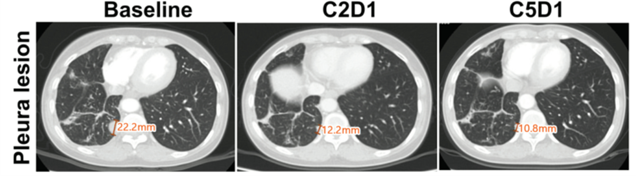

구체적으로는, 22.2mm의 폐에 있던 종양이 2개월 투약 후, 50% 이상 크기가 감소하였고, 뇌에 있던 병변은 10.6mm의 종양은 4개월 후 완전히 사라진 것을 확인했다.